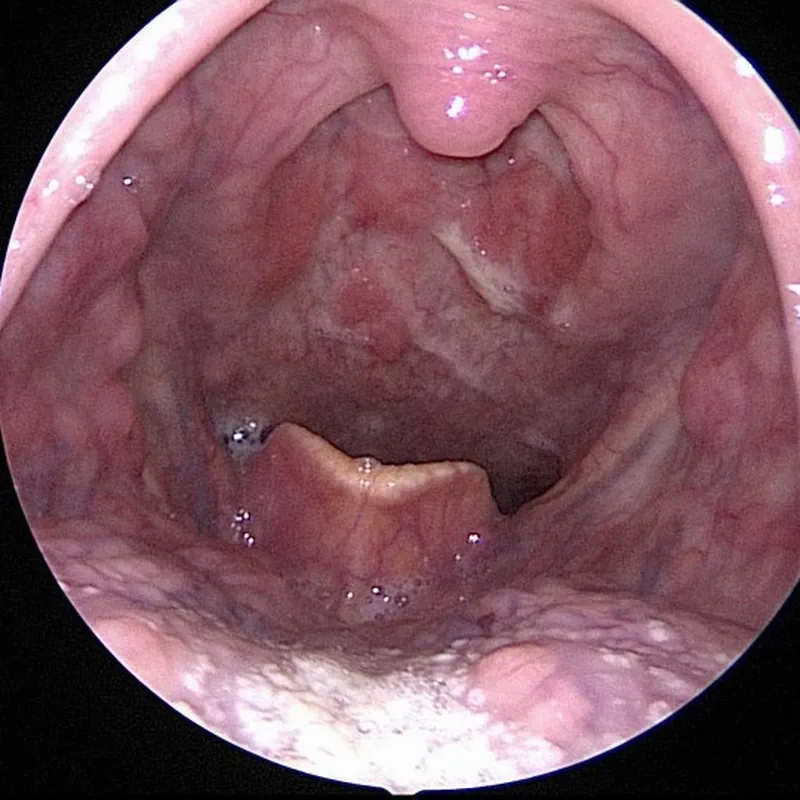

(땡큐서울의원에서 진단된 하인두암의 후두내시경 소견)